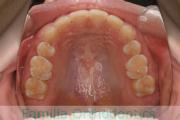

No.17V-474

- 主な症状:

- 上顎前突

- その他の症状:

- 過蓋咬合

- 年齢:

- 22歳

- 性別:

- 男性

- 抜歯部位

- 上:

- non

- 下:

- 88

- 主な使用装置:

- Invisalign

- 治療にかかった費用:

- 25万円

出っ歯を治したいということで小学生の時に来院されました。小学校高学年でヘッドギアを使って奥歯の位置を整えて、二期治療ではマウスピース型矯正装置のひとつ、インビザライン/Invisalign®(薬機法および医薬品副作用被害救済制度の対象外)を使用して治療を行いました。約1年半、20回程度の通院が必要でした。

- ≫治療前

上顎

下顎